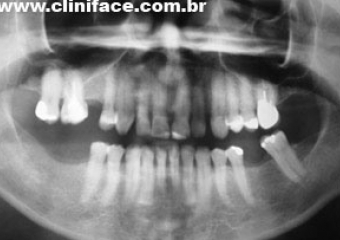

Raio X com implantes instalados